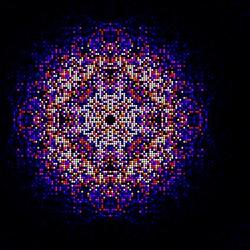

Kombinierte Intensitätskarte aus fast 200 000 Streubildern von in vivo gezüchteten Kristallen des Enzyms Cathepsin B aus dem Erreger der Schlafkrankheit. Diese Karte diente dazu, die dreidimensionale molekulare Struktur des Enzyms zu bestimmen. Bild: Karol Nass, CFEL

293 195 Beugungsbilder

Um die Struktur der Peptid-Bindestelle am Cathepsin B zu bestimmen, mussten die Forscher Hunderttausende Beugungsbilder aufnehmen und nachträglich zusammenfügen, wobei jedes Bild immer nur einen Teil der Struktur liefert. Da die Kristalle durch den Beschuss mit den Röntgenblitzen sofort verdampfen, ließen die Forscher Millionen von Kristallen in einem feinen Wasserstrahl durch den Strahl des Röntgenlasers rieseln. Der Röntgenlaser feuerte 120 Blitze pro Sekunde auf den Strahl, im Schnitt traf jeder elfte einen Kristall. So entstanden insgesamt 293 195 Beugungsbilder, die nur mit einem großen Parallelrechner verarbeitet werden konnten. Die Kombination ergibt zunächst eine dreidimensionale Karte der kompletten Streueigenschaften des Enzyms, aus der sich seine Struktur bis auf 2,1 Ångström genau berechnen ließ (ein Ångström ist ein zehntel Nanometer, das entspricht einem zehnmillionstel Millimeter). "Interessanterweise fällt unsere Entdeckung gerade mit dem hundertsten Jubiläum der Veröffentlichung der berühmten Röntgenbeugungsgleichung durch William Bragg im Jahr 1912 zusammen", betont Chapman.